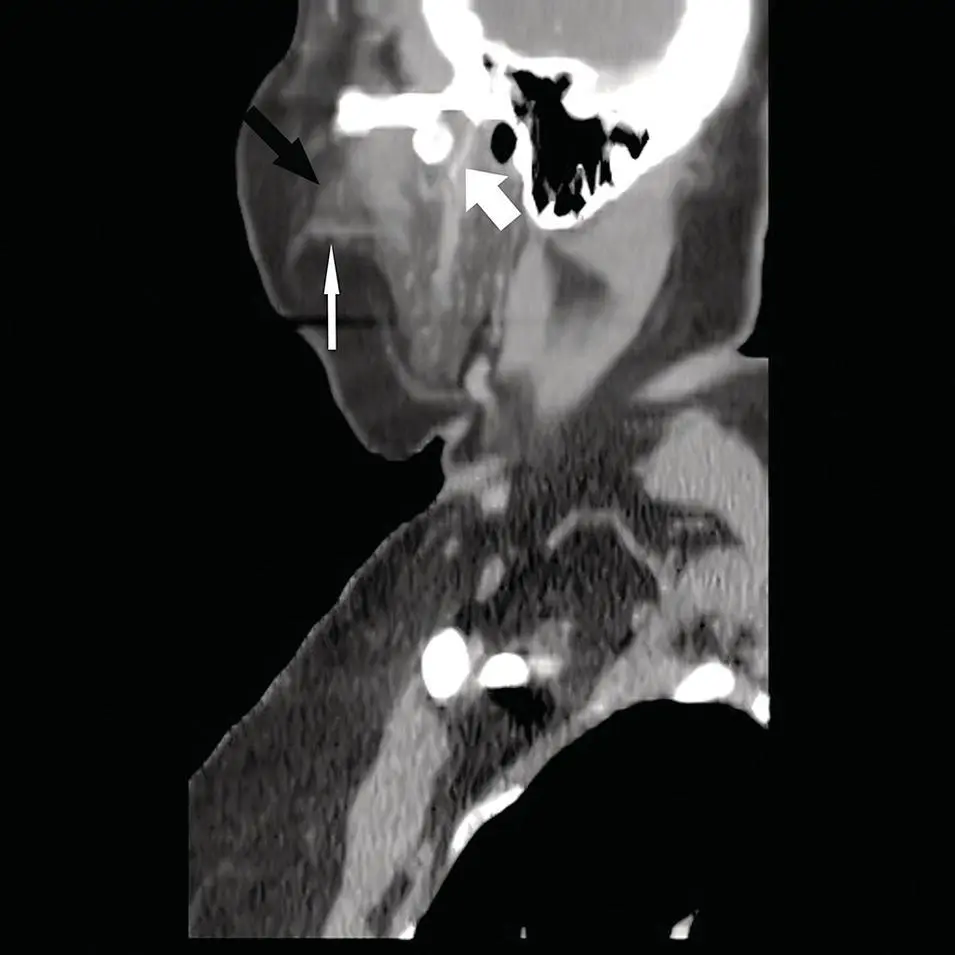

Figure 2.6. Sagittal CT reformation of the neck in soft‐tissue window at the level of the parotid gland. Note the accessory parotid gland (black arrow) sitting atop the parotid (Stensen) duct (thin white arrow). Also, note the retromandibular vein (large white arrow) and external auditory canal.